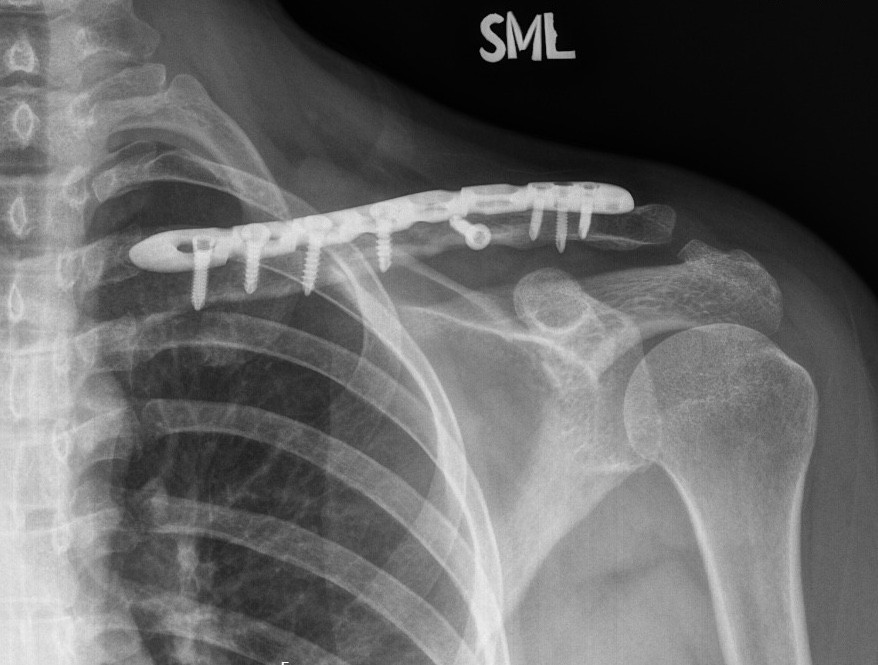

X-rays: To detect fractures or dislocations

Repair of fractures, dislocations, tendons, or ligaments